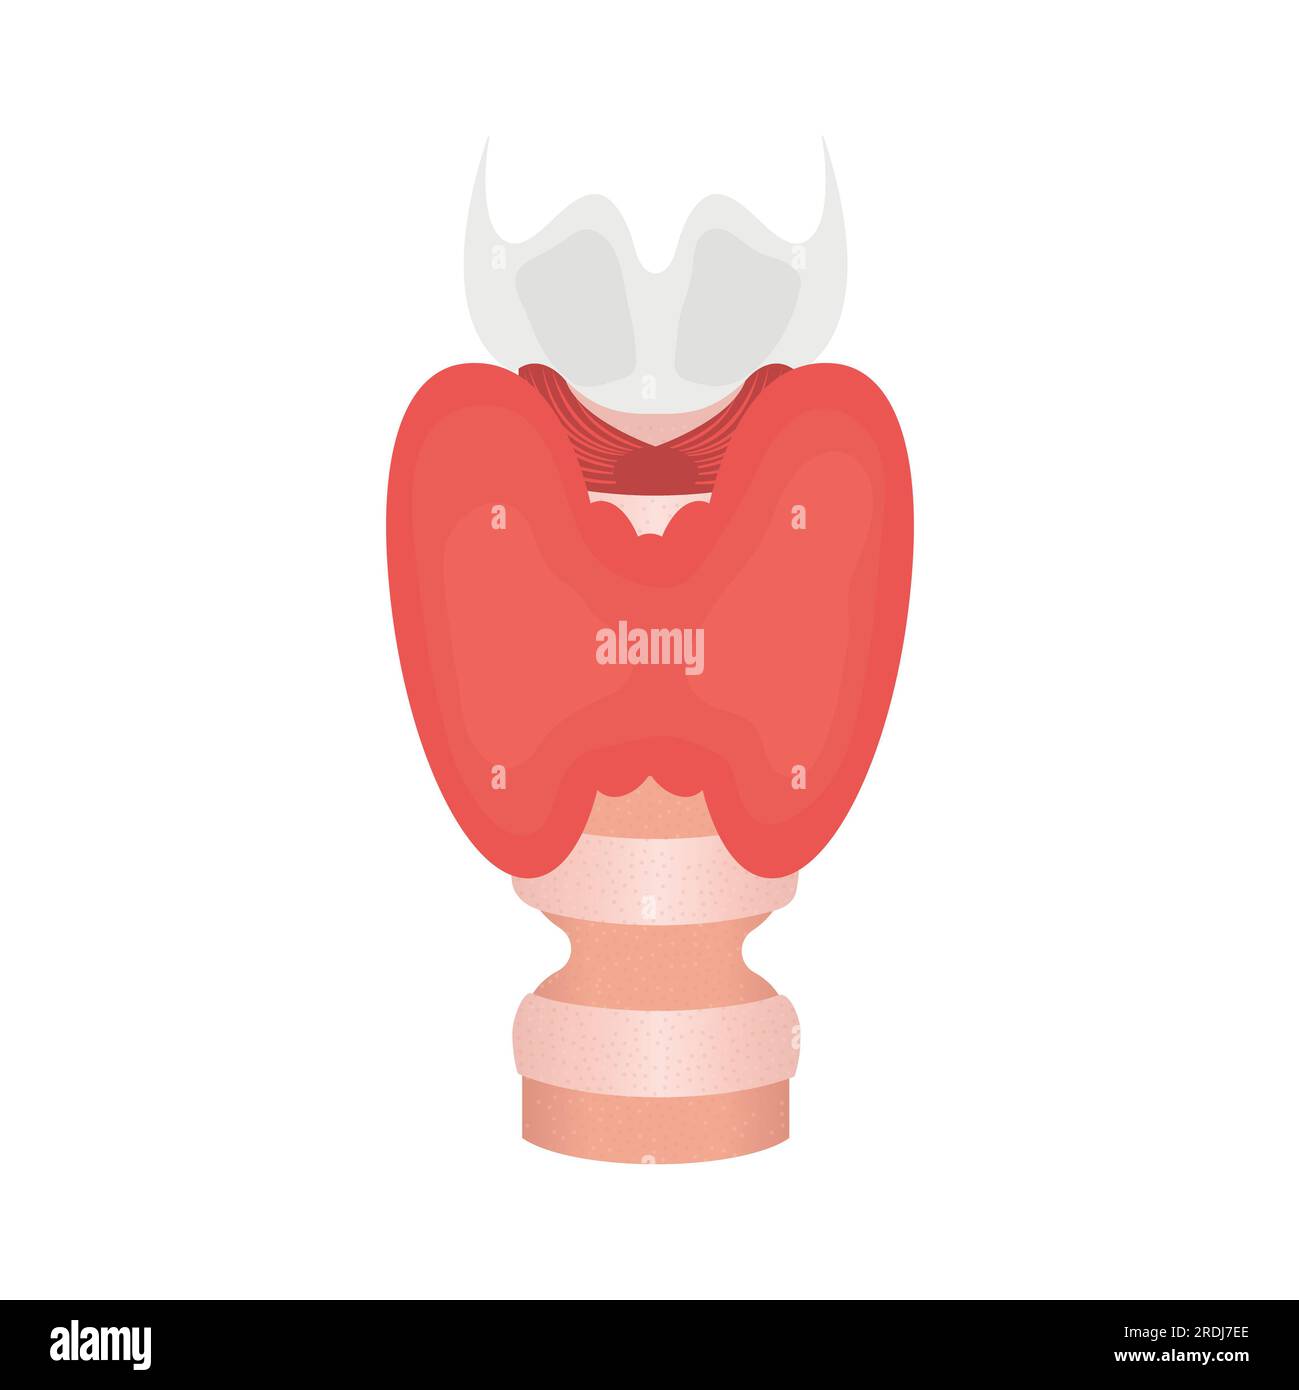

Tracheal stenosis, illustration Stock Photohttps://www.alamy.com/image-license-details/?v=1https://www.alamy.com/tracheal-stenosis-illustration-image559123334.html

Tracheal stenosis, illustration Stock Photohttps://www.alamy.com/image-license-details/?v=1https://www.alamy.com/tracheal-stenosis-illustration-image559123334.htmlRF2RDJ7EE–Tracheal stenosis, illustration